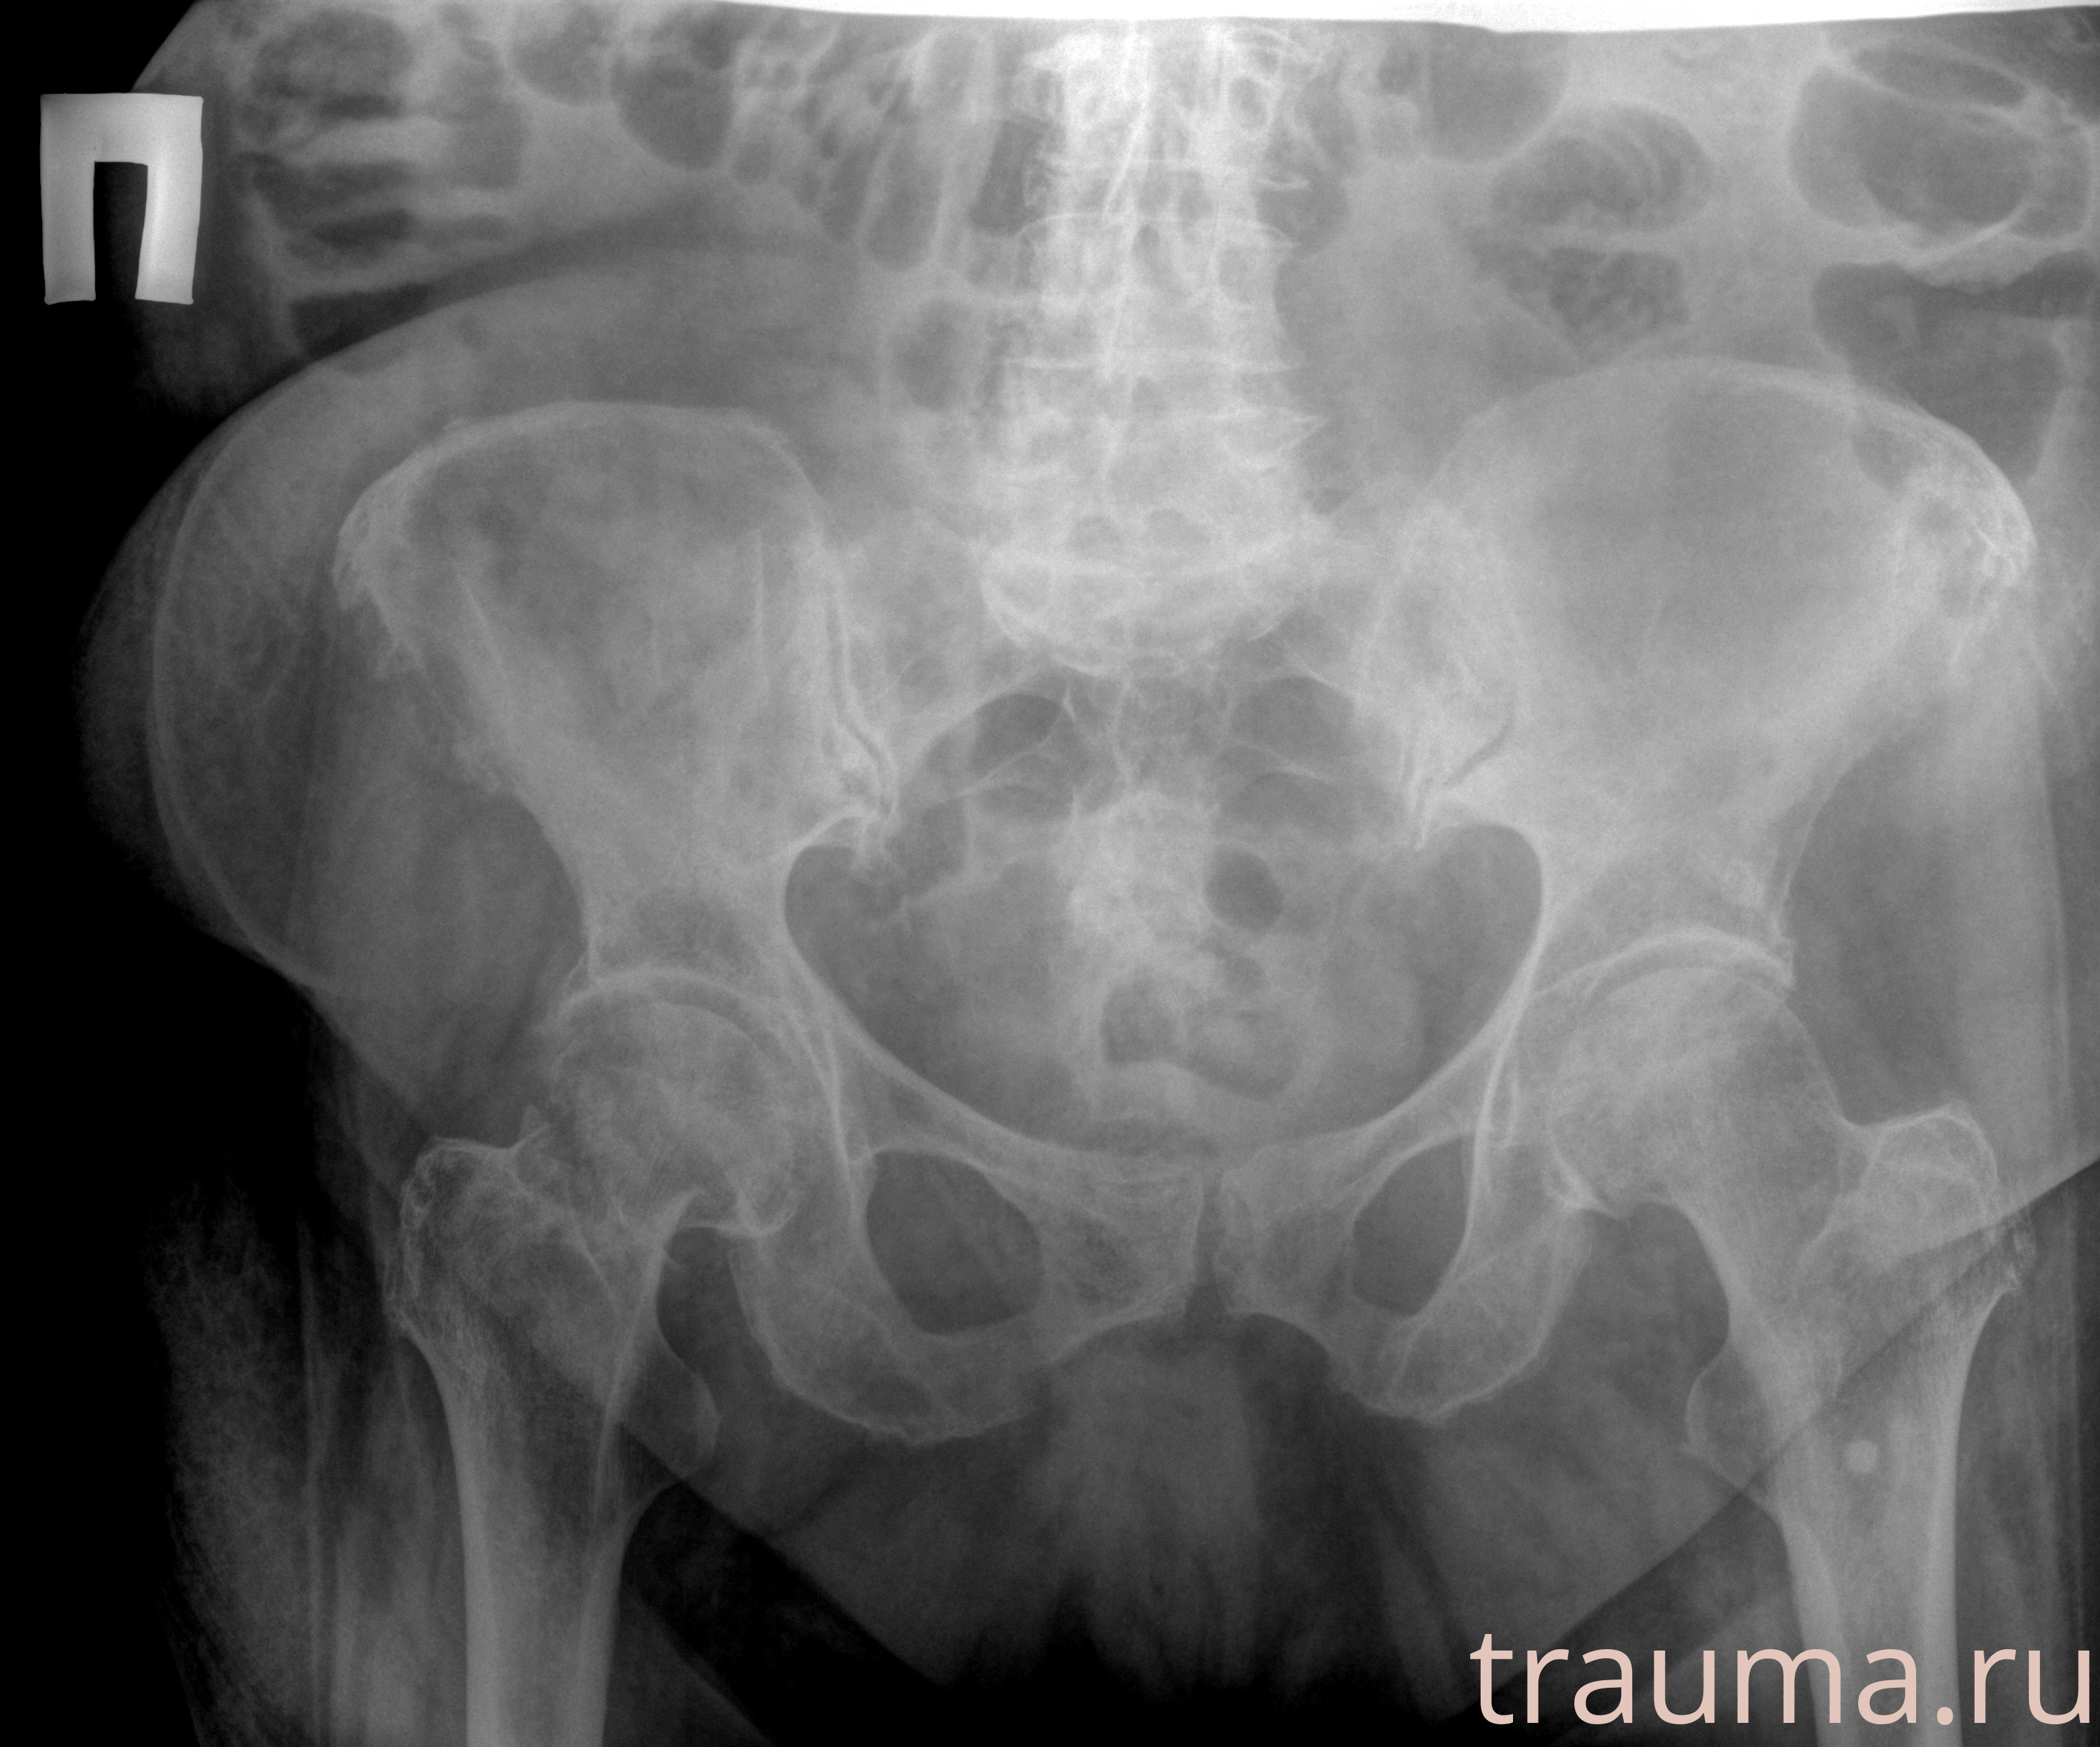

Рентгенограммы

Рентген на дому: по вашему адресу приезжает врач-рентгенолог, травматолог-ортопед с мобильным рентгеновским аппаратом, проводит диагностику травмы или заболевания, делает необходимые рентгенограммы, дает рекомендации по дальнейшему лечению. Получить качественные снимки в домашних условиях возможно благодаря уникальной методике, разработанной МосРентген Центром для института  Склифосовского